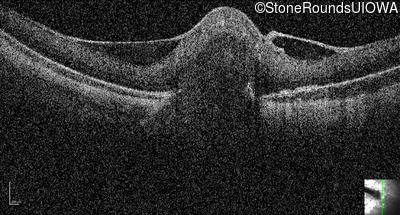

Optical Coherence Tomography - Left - 20/200

Exemplar